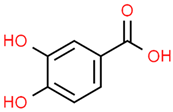

| 12 | Protocatechuic acid | 72 | C7H6O4 | 154.12 | C1=CC(=C(C=C1C(=O)O)O)O |  |